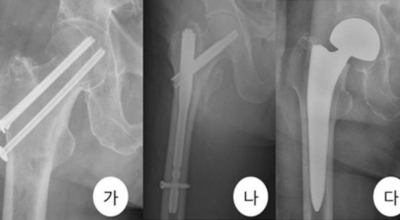

각별히 젊은 남성에게 잘 발생하며 엉덩이와 골반 주위에 뻐근한 통증이 동반되며 정상적인 보행이 되지 않고 절뚝거리는 증상이 나타난다면 대퇴골두 무혈성 괴사일 가능성이 있답니다. 이 증상은 괴사 부위의 골절이 발생되어 고관절 손상으로 이어지면 발생하는 증상으로 아직까지 정확한 원인은 규명하기 힘드나 과음이나 고지혈증, 스테로이드 과남용이 영향을 줄 수 있어요.

그러나 비수술 치료법으로 개선시키는 것이 어려운 경우 수술적 방법이 고려됩니다. 고관절 통증을 조기에 치료하면 약물치료 외에 물리치료로 약 50% 정도 큰 효과를 볼 수 있어요. 게다가, 보통 고관절 증상 관리에 도움되는 요가, 수영, 스트레칭은 고관절 예방과 치료에 도움 됩니다.